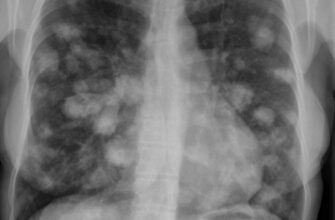

- Еозинофілія (підвищення рівня еозинофілів) вказує на алергічні реакції або паразитарні інфекції.